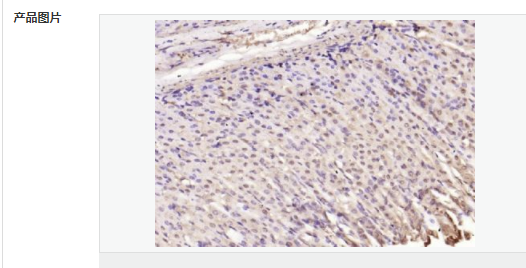

| 產(chǎn)品應(yīng)用 | ELISA=1:5000-10000 IHC-P=1:100-500 IHC-F=1:100-500 IF=1:100-500 (石蠟切片需做抗原修復(fù)) not yet tested in other applications. optimal dilutions/concentrations should be determined by the end user. |

| 免 疫 原 | KLH conjugated synthetic peptide derived from human SQSTM1/p62:51-150/440 |